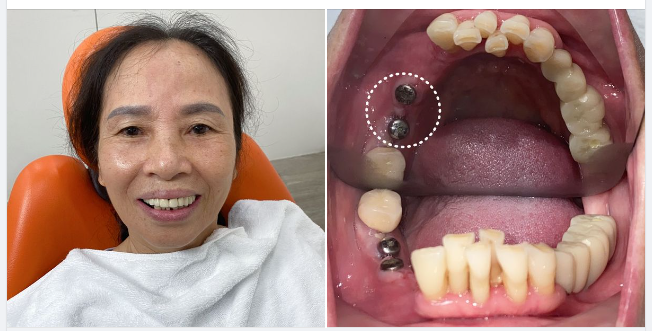

Trồng Răng Implant

Trồng Răng Implant -